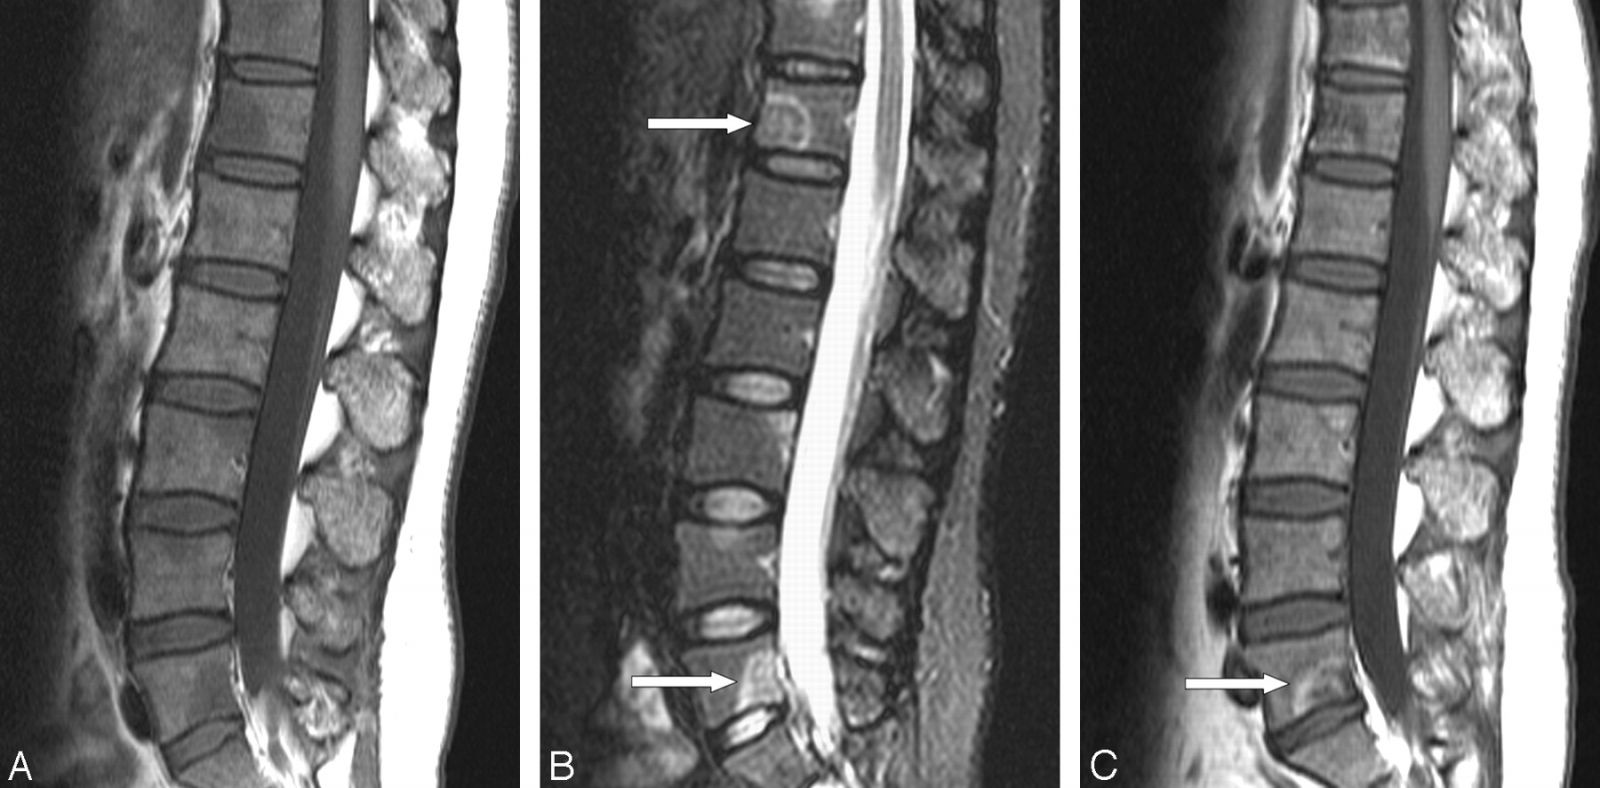

Магнитно-резонансная томография считается «золотым стандартом», позволяя выявить воспаление на ранних стадиях, оценить вовлечение дисков, паравертебральных тканей и спинного мозга.